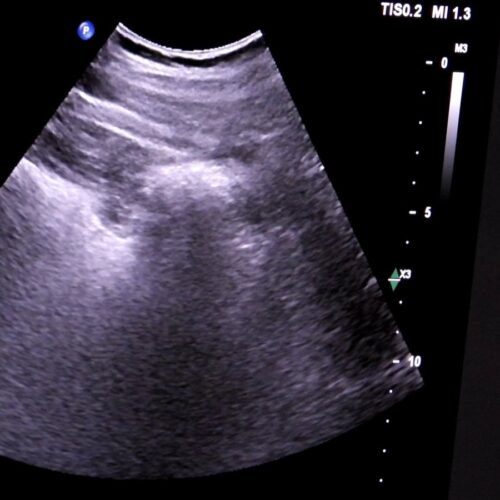

Tokom tri sedmice pregleda obavljenih u Edukacijskom centru KBZ-a, detaljnim pregledima je pristupilo 200 građana. Ultrazvuk abdomena je brz, bezbolan i siguran način da se provjeri stanje unutrašnjih organa, poput jetre, bubrega, gušterače i žučne kese.

Ultrazvuk abdomena je jednostavna, bezbolna i sigurna metoda pregleda pomoću koje možemo pregledati organe i strukture koji se nalaze unutar trbušne šupljine. Ovaj pregled igra važnu ulogu u ranom otkrivanju promjena koje mogu dovesti do narušavanja zdravlja i razvoja bolesti.